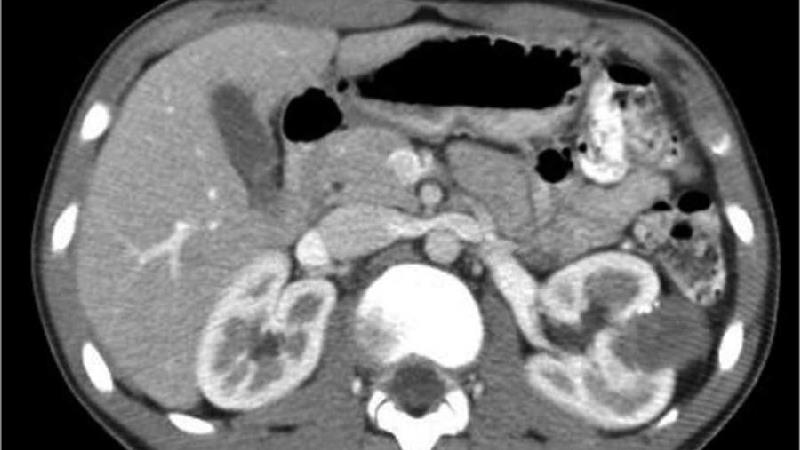

در این مرحله بیماری با استفاده از تست هایی نظیر تشخیصی و افتراقی و روش های رادیوگرافی، سونوگرافی و سی تی اسکن شناسایی شود.